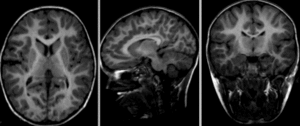

RegLib C42 Xf2 registered.gif after nonrigid BSpline registration (click to enlarge)

RegLib C42 Xf2a DeformOnly.gif| visualization of the nonrigid deformation component only